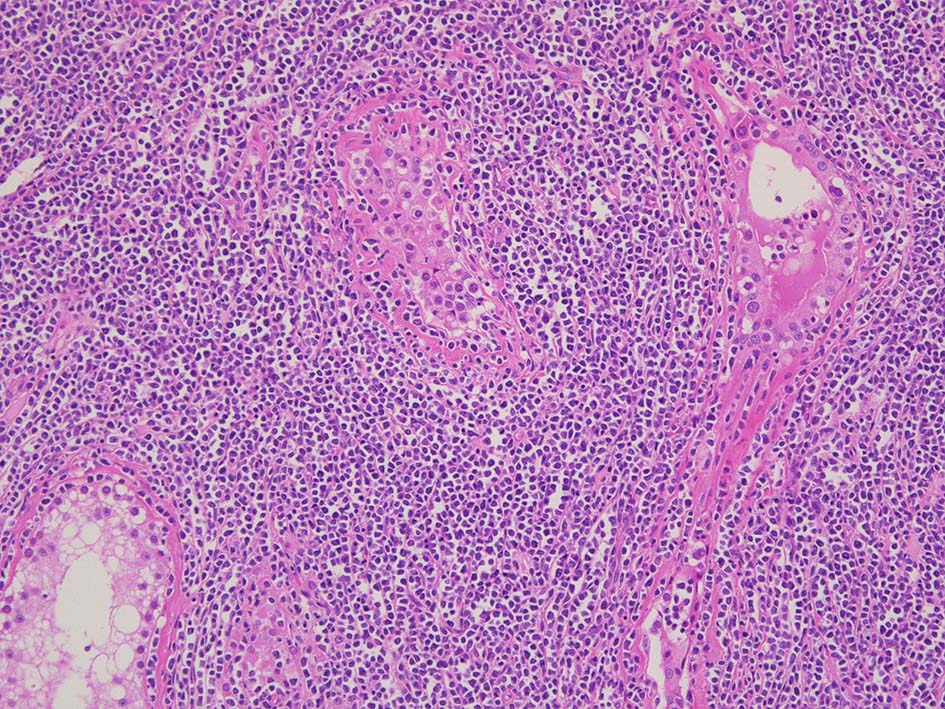

光顕所見; リンパ腫により, 少なくとも一部の領域の精細管が消失する. 末梢の領域では精細管の間質にリンパ腫細胞が浸潤する. ほとんどの場合、腫瘍細胞は精細管に侵入, 精細管の周辺を占め、生殖細胞とセルトリ細胞を中央に変位させるか, または精細管を完全に占拠してしまう.

増殖巣では精細管は消失, 萎縮. 腫瘍境界部での浸潤所見がある.

精細管の多くがスペアされ, 間質にlymphoid cellsが密に浸潤している. わずかな精細管に浸潤が認められ萎縮や破壊像が認められる. 精細管において Lymphoepithelial lesion(LEL)に似た所見がある.